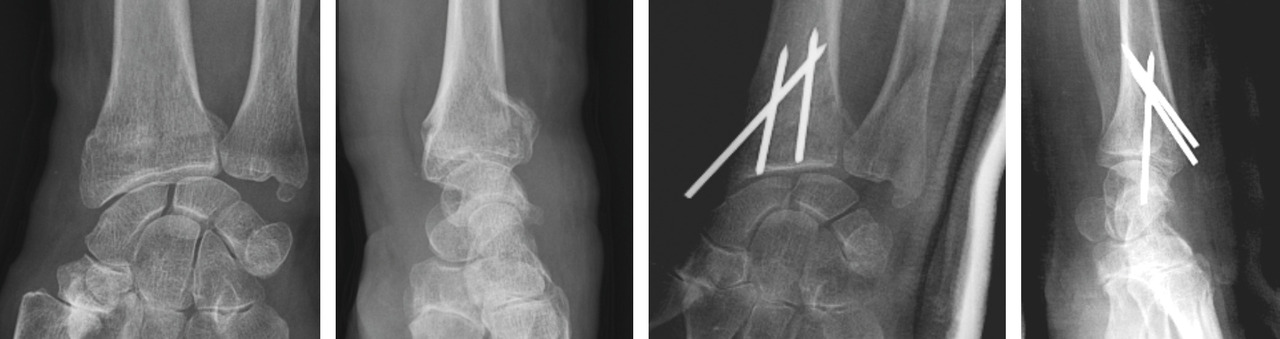

La mise en place des broches percutanées sont habituellement introduites dans le foyer de fracture, en arrière du radius, puis inclinées vers le bas pour réduire la bascule dorsale de la glène radiale et sont finalement fichées dans la corticale antérieure, épaisse, pour stabiliser la réduction obtenue. Il s’agit d’un embrochage « intrafocal » (dans le foyer de fracture). Une ou deux broches styloïdiennes dans le plan frontal complètent le montage. La bascule antérieure du fragment distal, la présence de refends articulaires, et la comminution métaphyso-épiphysaire sont indispensables à évaluer avant de proposer ce type de traitement et constituent des contre-indications relatives (fig. 12).